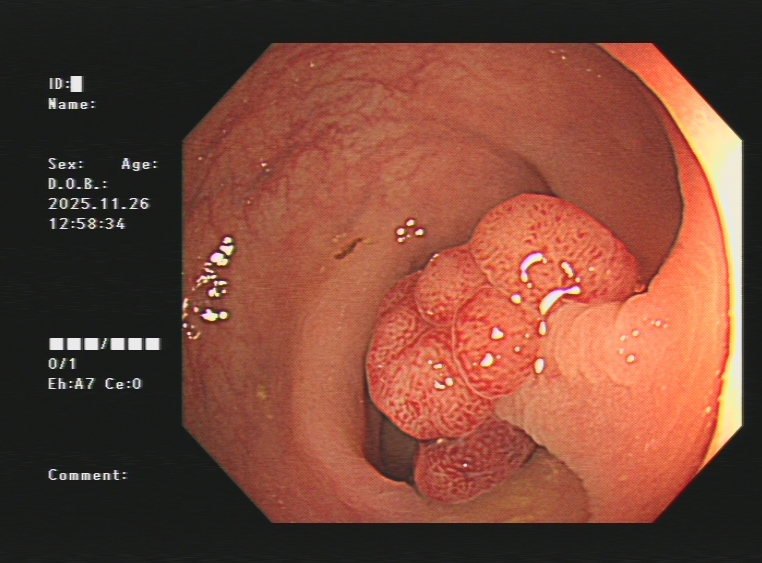

3.下消化道出血常见病因包括痔疮、肛裂、肠息肉、结肠癌、肠道憩室、炎症性病变(溃疡性结肠炎、缺血性肠炎、 感染性肠炎等)。以下是一些常见的下消化道出血内镜图片:

结肠息肉出血镜下切除